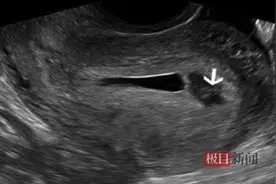

极目新闻记者 郑晶晶通讯员 陈晶 江向群 魏星怀孕12周左右的许女士日前突然出现腹胀的情况,紧急就医后,经过检查被发现原来患上了绒毛膜下血肿、先兆流产,幸经及时救治后转危为安。医生详细询问后才知道,这竟跟她锻炼过量密不可分。